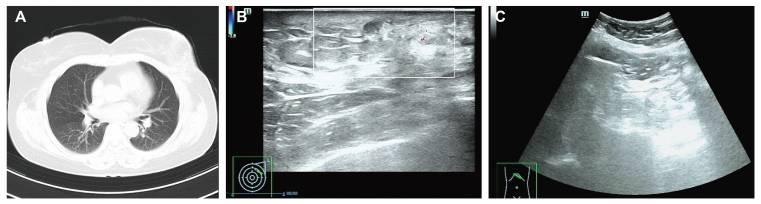

截至2025年5月,随访评估,包括胸部CT、乳房和腹部超声检查以及血清肿瘤标志物评估,均未发现复发或转移的证据。最近的肿瘤标志物水平在正常范围内:CEA为3.05 ng/ml(参考值,<4.7 ng/ml);CA15-3为19.6U/ml(参考值<26.2U/ml)。2025年5月的放射学随访成像也没有发现异常:胸部CT显示没有肺或纵隔转移的证据(图4A),乳房超声检查显示左乳房术后变化,没有局部复发的迹象(图4B),腹部超声检查没有发现肝或腹膜病变(图4C)。此外,根据2024 CSCO乳腺癌症指南,建议患者继续接受基于AI的内分泌治疗5年,以及随访监测计划,包括每3个月进行一次乳腺超声检查,每6个月进行乳腺MRI和肿瘤标志物评估。

图4 患者的放射学随访成像。(A)胸部计算机断层扫描显示没有肺或纵隔转移的证据。(B)乳房超声检查显示左乳房术后变化,无局部复发迹象。(C)腹部超声检查显示无肝脏或腹膜异常